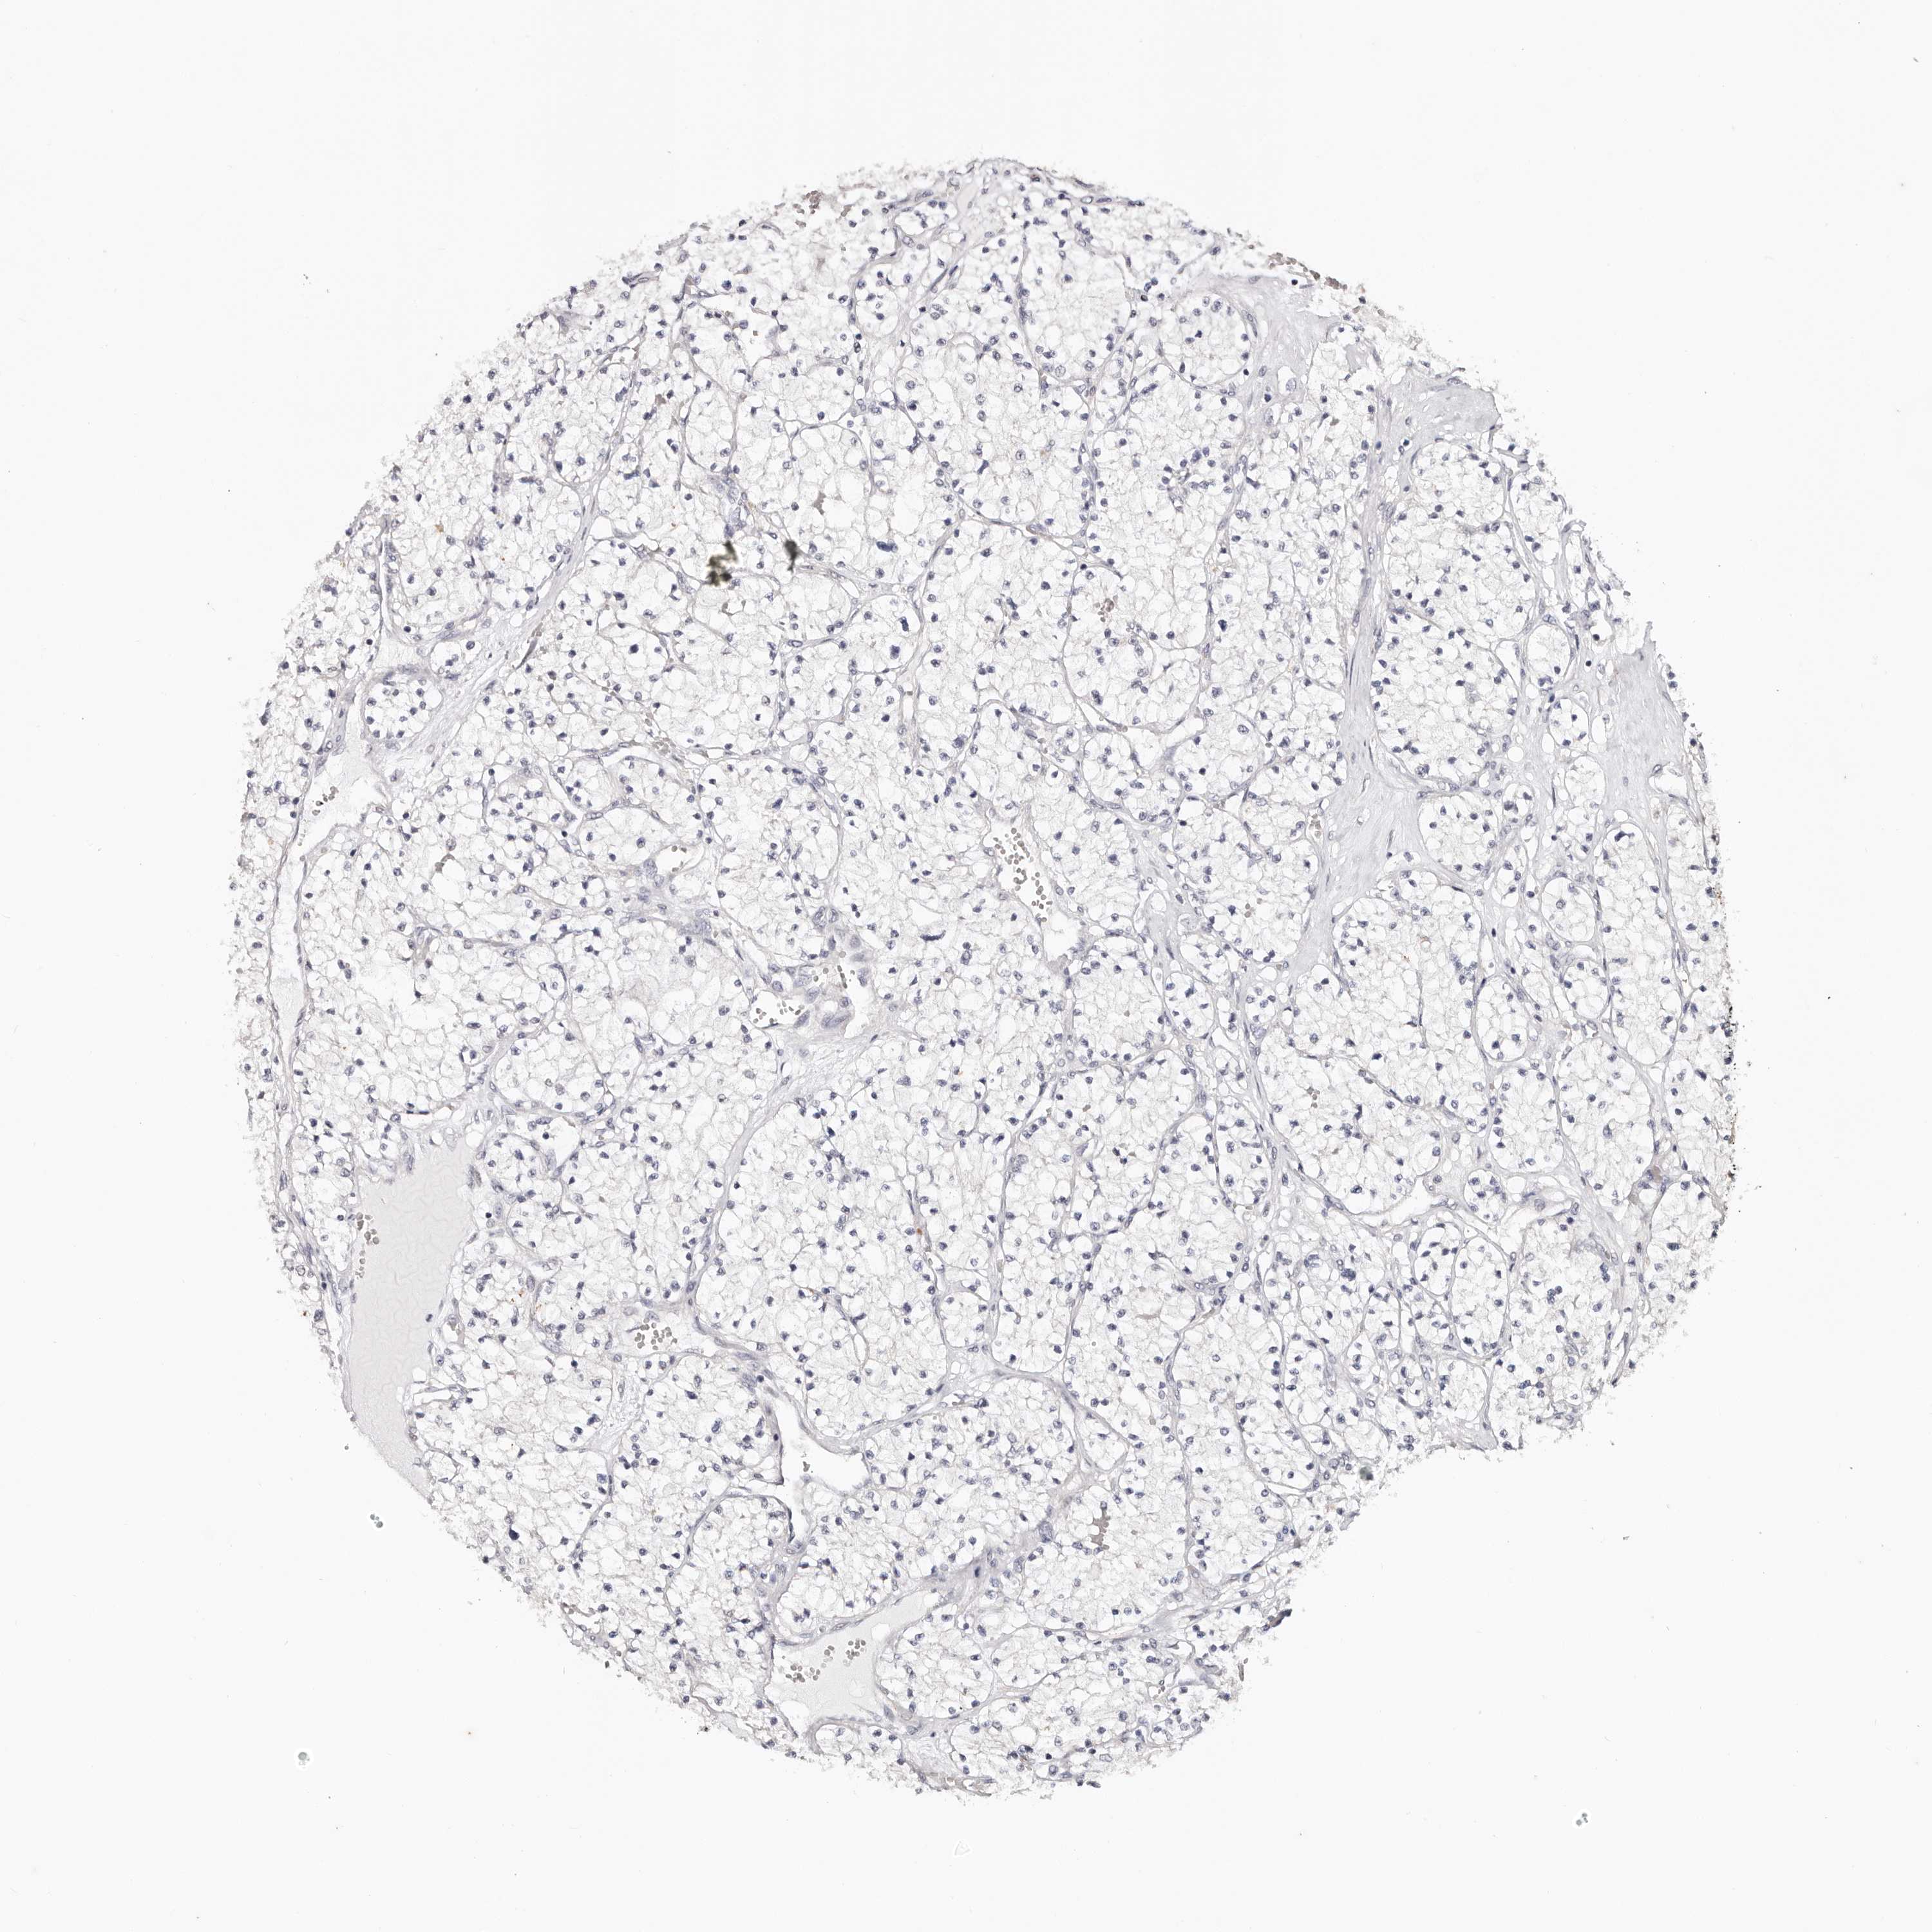

KIDNEY RENAL PAPILLARY CELL CARCINOMA (TCGA) - Interactive survival scatter ploti

The Survival Scatter plot shows the clinical status (i.e. dead or alive) for all individuals in the patient cohort, based on the same data that underlies the corresponding Kaplan-Meier plots. Patients that are alive at last time for follow-up are shown in blue and patients who have died during the study are shown in red.

The x-axis shows the expression levels (FPKM) of the investigated gene in the tumor tissue at the time of diagnosis. The y-axis shows the follow-up time after diagnosis (years). Both axes are complimented with kernel density curves demonstrating the data density over the axes. The top density plot shows the expression levels (FPKM) distribution among dead (red) and alive patients (blue). The right density plot shows the data density of the survived years of dead patients with high and low expression levels respectively, stratified using the cutoff indicated by the vertical dashed line through the Survival Scatter plot. This cutoff is automatically defined based on the FPKM cutoff that minimizes the p-score. The cutoff can be changed by dragging the vertical line or by entering a cutoff value in the square labeled "Current cut-off".

Under the Survival Scatter plot the p-score landscape (black curve; left axis) is shown together with dead median separation (red curve; right axis). Dead median separation is the difference in median mRNA expression between patients who have died with high and low expression, respectively. It is calculated as follows: median FPKM expression of dead patients with high expression - median FPKM expression of dead patients with low expression. This is intended to aid the user in visually exploring custom cutoffs and the associated p-scores and dead median separation.

Individual patient data is displayed and can be filtered by clicking on one or more of the category buttons on the top of the page. Categories describing expression level and patient information include: high, low, alive, dead, female, male and tumor stages. The scale of the x-axis can be toggled between linear and log-scale by clicking on the "x log" button. Mouse-over function shows TCGA ID, patient information and mRNA expression (FPKM) for each patient.

& Survival analysisi

Kaplan-Meier plots summarize results from analysis of correlation between mRNA expression level and patient survival. Patients were divided based on level of expression into one of the two groups "low" (under cut off) or "high" (over cut off). X-axis shows time for survival (years) and y-axis shows the probability of survival, where 1.0 corresponds to 100 percent.

TYW3 is potential prognostic, high expression is unfavorable in Kidney Renal Papillary Cell Carcinoma (TCGA)

Best expression cut offi

Based on the FPKM value of each gene, patients were classified into two groups and association between prognosis (survival) and gene expression (FPKM) was examined. The best expression cut-off refers the FPKM value that yields maximal difference with regard to survival between the two groups at the lowest log-rank P-value. Best expression cut-off was selected based on survival analysis .

When clicking on this number, the vertical dashed line indicating cut-off, the interactive survival plot, and the Kaplan-Meier curve will be adjusted to show results based on the best expression cut-off.

: 13.43

Median expressioni

Median expression refers to the median FPKM value calculated based on the gene expression (FPKM) data from all patients in this dataset. When clicking on this number, the vertical dashed line indicating cut-off, the interactive survival plot, and the Kaplan-Meier curve will be adjusted to show results based on the median expression.

: N/A

Median follow up timei

Median follow up time refers to the median time (years) after diagnosis with this type of cancer, based on clinical data from all patients in this dataset.

P scorei

Log-rank P value for Kaplan-Meier plot showing results from analysis of correlation between mRNA expression level and patient survival.

N/A

5-year survival highi

5-year survival for patients with higher expression than the expression cutoff.

For melanoma and glioma, 3-year survival is shown.

5-year survival lowi

5-year survival for patients with lower expression than the expression cutoff.

TCGA RNA samplesi

RNA-seq data is reported as average FPKM (number Fragments Per Kilobase of exon per Million reads), generated by the The Cancer Genome Atlas (TCGA) .

Normal distribution across the dataset is visualized with box plots, shown as median and 25th and 75th percentiles. Points are displayed as outliers if they are above or below 1.5 times the interquartile range. FPKM values of the individual samples are presented next to the box plot.

Average pTPM 10.5

Number of samples 282

Samples

Sample Description pTPM

TCGA-5P-A9JU-01A 81 years, male, white, stage:Stage III, alive, 373 days 42.5

TCGA-B3-4104-01A 75 years, male, white, stage:Stage II, alive, 1049 days 32.0

TCGA-B3-4103-01A 56 years, male, white, stage:Stage I, alive, 930 days 27.7

TCGA-F9-A97G-01A 79 years, male, asian, stage:Stage III, alive, 13 days 27.4